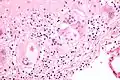

Micrograph of asteroid bodies in pulmonary sarcoidosis. H&E stain. Micrograph of asteroid bodies in pulmonary sarcoidosis. H&E stain.

Micrograph of asteroid bodies in pulmonary sarcoidosis. H&E stain. Asteroid body in sarcoidosis.